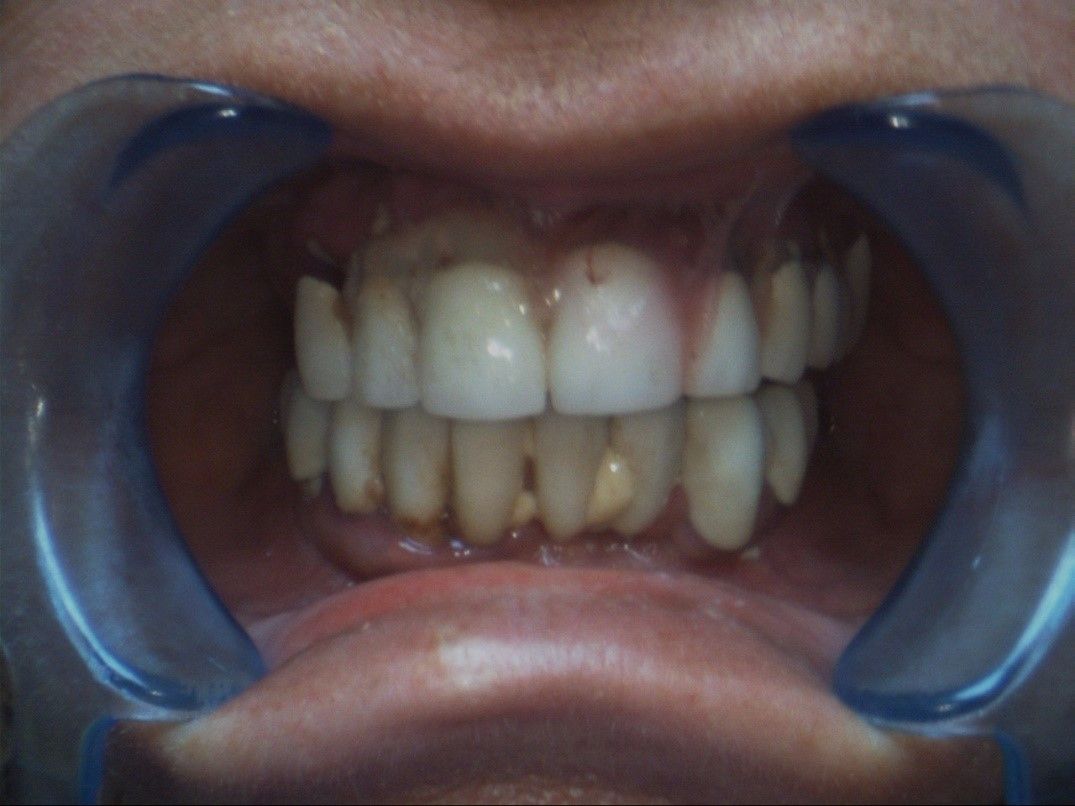

В наш Центр обратилась пациентка с частичным отсутствием зубов. С жалобами на затруднённое пережевывание пищи, неприятный запах изо-рта и неудовлетворительный эстетический вид зубов. Мы сделали бесплатное цифровое исследование полости рта, бесплатные цифровые компьютерные снимки.

При этих исследованиях мы выяснили, что большинство зубов в полости рта отсутствуют, есть старые коронки, которые расцементировались. Под коронками увидели тёмные пятна – это говорит о том, что зубы под коронками уже практически полностью рассыпались и исчезли. Там же увидели ещё два старых имплантанта, которые реинтегрировались.

фото до операции